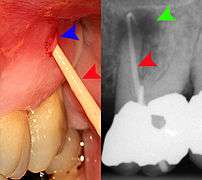

Decay (green) with apical abscess (blue)

Gutta-percha point indicating abscess origin

The periodontal ligament becomes inflamed and there may be pain when biting or tapping on the tooth. On an X-ray, bone resporption appears as a radiolucent area around the end of the root, although this does not manifest immediately.[9]:228 Acute apical periodontitis is characterized by well-localized, spontaneous, persistent, moderate to severe pain.[4]:125–135 The alveolar process may be tender to palpation over the roots. The tooth may be raised in the socket and feel more prominent than the adjacent teeth.[4]:125–135

- Radiographs utilized to find dental caries and bone loss laterally or at the apex.